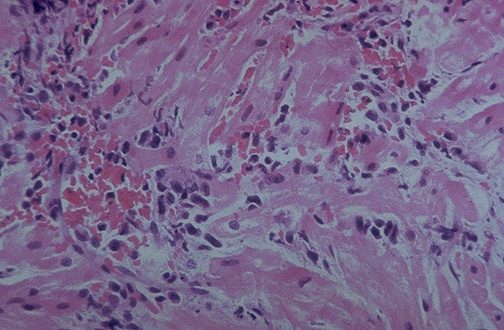

| This is acute vascular rejection in a heart transplant. The inflammatory reaction consists mostly of lymphocytes and is seen mainly around small arteries, a vasculitis. Such a reaction can occur when the dose of immunosuppressive drugs is decreased in the months following transplantation. Increasing immunosuppresive therapy in these patients is not as effective as for acute cellular rejection. |